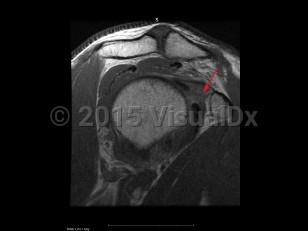

Classic history and presentation: Adhesive capsulitis typically follows a course of 3 phases. First (2-9 months), there is an insidious onset of pain that eventually becomes severe and disabling. The pain tends to be worse at night and stiffness gradually onsets. Second (4-12 months) is the contracture phase, which is characterized by stiffness and progressive loss of motion that interferes with activities of daily living. Pain typically improves in this phase. Third (5-24 months) is the recovery or "thawing" phase in which the symptoms gradually alleviate and there is an improvement in range of motion (ROM).

Grade / classification system: Adhesive capsulitis can be classified as primary, which is idiopathic, and secondary, which is onset due to trauma or immobilization.